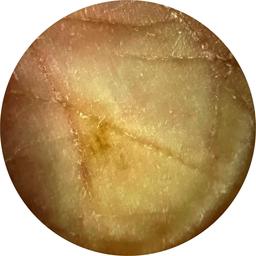

ISIC_7213120

Clinical

Field Value

acquisition_day 277

age_approx 70

anatom_site_1 Lower extremity

anatom_site_general lower extremity

diagnosis_1 Benign

family_hx_mm True

fitzpatrick_skin_type I

image_manipulation instrument only

image_type dermoscopic

lesion_id IL_3605610

patient_id IP_0257923

personal_hx_mm True

sex female